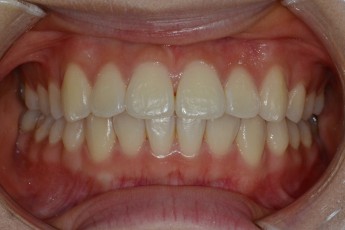

Before

After